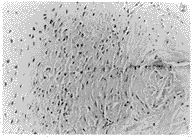

4.病理组织学检查 空白组:肌束间组织广泛水肿,伴有轻度的炎症反应,血管和成纤维细胞增生,肌纤维束间纤维组织增生明显,并形成类骨组织和类软骨组织,肌束间增生的纤维组织中局部出现异位骨化,骨化灶呈不规则分布,并可见纤维性成骨的移行区(图2)。用药组:肌组织内肌束间纤维增生,增生的纤维组织局部有骨化倾向并形成类软骨样组织,但无明显骨化出现(图3)。

图2 空白组:肌束间组织广泛水肿,肌纤维束间纤维组织增生明显,并形成类骨组织和类软骨组织,出现异位骨化。HEx40

图3 用药组:增生的纤维组织中局部仅有少许类骨组织和类软骨样组织,无明显骨化出现。HEx250